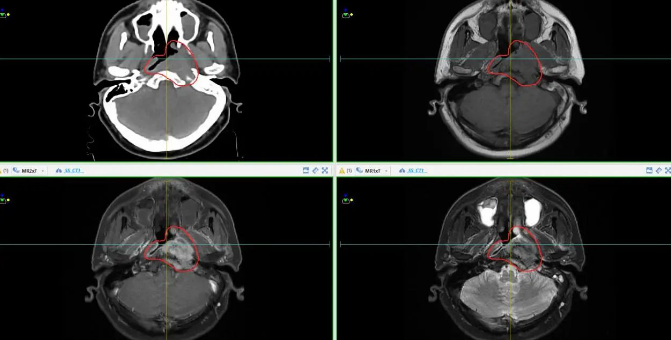

常态化磁共振模拟定位(实现放疗靶区雕刻式精准勾画)

鼻咽癌伴颈部淋巴结、胰头淋巴结及肝转移治疗前后对比